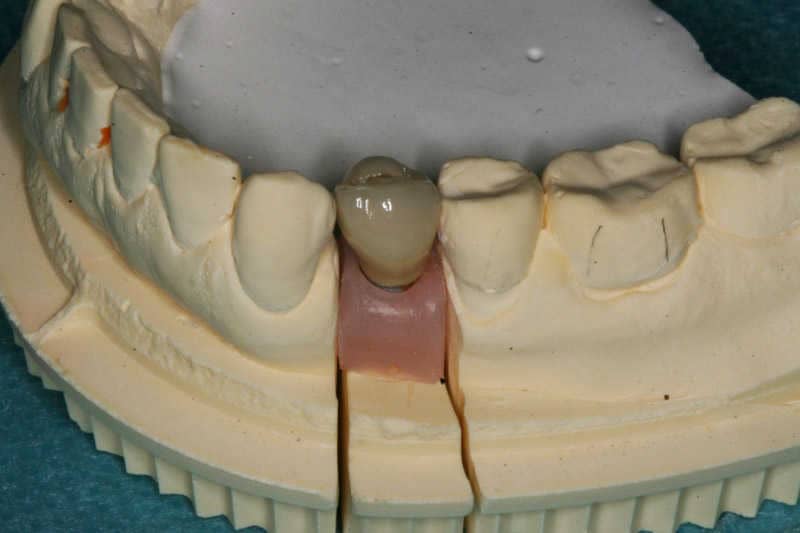

3

Az elkészült fémkerámia pótlás a gipszmintán